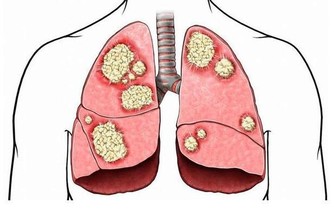

談到心肌梗塞,大家總是把這個好發於寒冷季節的疾病,跟年長的男性聯想在一起。

根據研究,女性罹患心肌梗塞的症狀其實和男性並不相同,以致於很容易被忽略而失去了搶­救的先機。

到底兩性有哪些不同的症狀?

還有,心肌梗塞一定都是突然發作的嗎?

我們能不­能從外表找到發病的前兆呢?